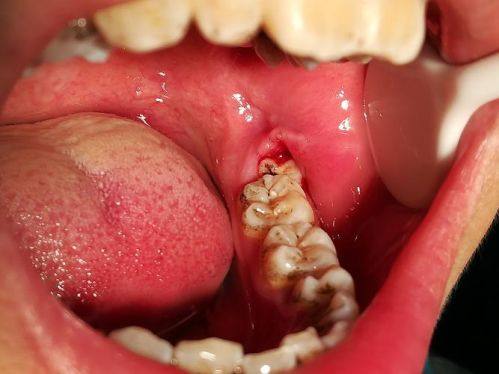

然而,如果智齿存在阻生情况,像水平阻生、倒置阻生等,那就可能是个“小麻烦”了。这类智齿常常会引发智齿冠周炎,让牙龈变得红肿、疼痛,还会影响周围组织的健康。更重度的是,它可能会压迫邻牙,导致邻牙的牙根被吸收,或者出现龋坏等问题。从长远来看,为了确保矫正成效和口腔的整体健康,一般建议把这样的智齿拔掉。